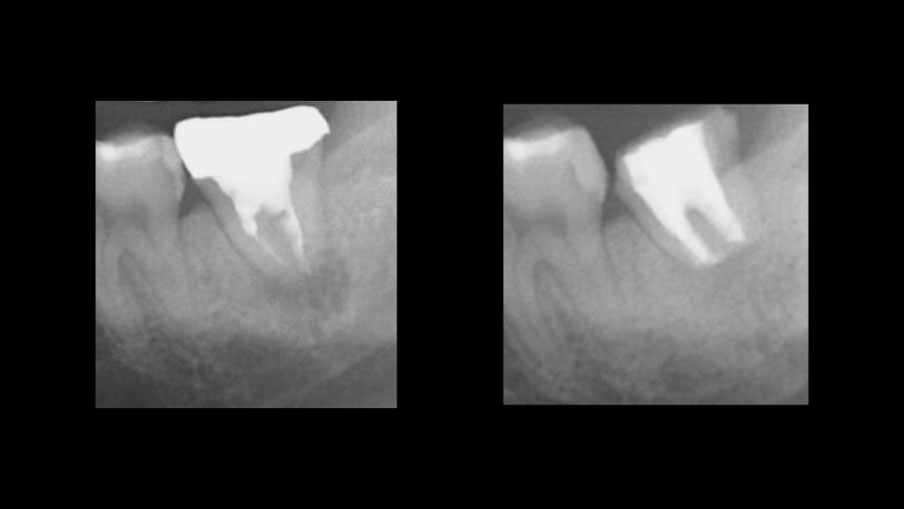

症例3 根の病変で抜歯と

言われた歯の保存

• 主訴

痛くて噛めない

• 診断

慢性根尖性歯周炎

• 治療 感染根管治療、歯根端切除術

• 治療期間

3ヶ月

• 治療費

約16万円

• リスク

再発の可能性あり

歯質量が少ない場合は破折の可能性あり

根の病変で抜歯と言われた歯の保存

before    after